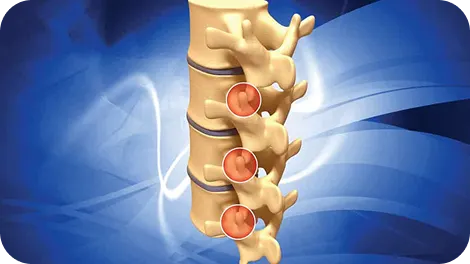

Targeted history & exam to identify disc/nerve/joint drivers

Fluoro-guided spine/SI procedures when indicated

Imaging coordination only if results will change decisions

Usually not. We begin with a focused exam and coordinate imaging only when results will change management (e.g., progressive neurologic deficit, suspected structural compression, or stalled progress). This keeps care efficient and avoids unnecessary tests.

They’re not required. Most patients start with conservative care. When pain blocks progress or diagnosis needs clarity, fluoroscopy-guided injections can target inflamed nerves or joints, creating a window for rehab. They’re tools within a broader plan—not the whole plan.